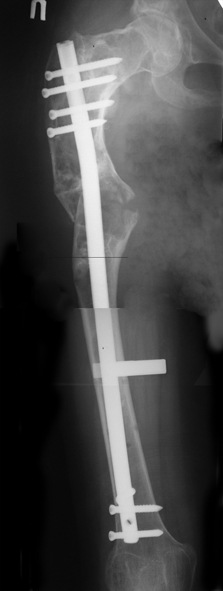

В ноябре этого года я обращался с просьбой о помощи в выборе тактики лечения больной с деформацией бедра на почве фиброзной дисплазии. Были получены интересные и очень полезные советы по операции.

Операция выполнялась с помощью А.Н.Челнокова. Очень понравилась технология выполнения блокируемого остеосинтеза с использованием спицевого дистрактора, модифицированный гвоздь с латерализованным проксимальным отделом и возможностью многовинтовой фиксации проксимального и дистального участков бедра.